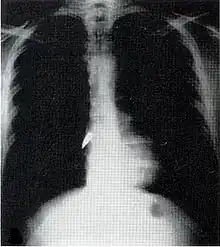

Chest

Most penetrating injuries are chest wounds and have a mortality rate (death rate) of under 10%.[14] Penetrating chest trauma can injure vital organs such as the heart and lungs and can interfere with breathing and circulation. Lung injuries that can be caused by penetrating trauma include pulmonary laceration (a cut or tear) pulmonary contusion (a bruise), hemothorax (an accumulation of blood in the chest cavity outside of the lung), pneumothorax (an accumulation of air in the chest cavity) and hemopneumothorax (accumulation of both blood and air). Sucking chest wounds and tension pneumothorax may result.

Penetrating trauma can also cause injuries to the heart and circulatory system. When the heart is punctured, it may bleed profusely into the chest cavity if the membrane around it (the pericardium) is significantly torn, or it may cause pericardial tamponade if the pericardium is not disrupted.[15] In pericardial tamponade, blood escapes from the heart but is trapped within the pericardium, so pressure builds up between the pericardium and the heart, compressing the latter and interfering with its pumping.[15] Fractures of the ribs commonly produce penetrating chest trauma when sharp bone ends pierce tissues.

Assessment can be difficult because much of the damage is often internal and not visible.[4] The patient is thoroughly examined.[2] X-ray and CT scanning may be used to identify the type and location of potentially lethal injuries.[2] Sometimes before an X-ray is performed on a person with penetrating trauma from a projectile, a paper clip is taped over entry and exit wounds to show their location on the film.[2] The patient is given intravenous fluids to replace lost blood.[2] Surgery may be required; impaled objects are secured into place so that they do not move and cause further injury, and they are removed in an operating room.[2] If the location of the injury is not obvious, a surgical operation called an exploratory laparotomy may be required to look for internal damage to the organs in the abdomen.[17] Foreign bodies such as bullets may be removed, but they may also be left in place if the surgery necessary to get them out would cause more damage than would leaving them.[12] Wounds are debrided to remove tissue that cannot survive and other material that presents risk for infection.[2]